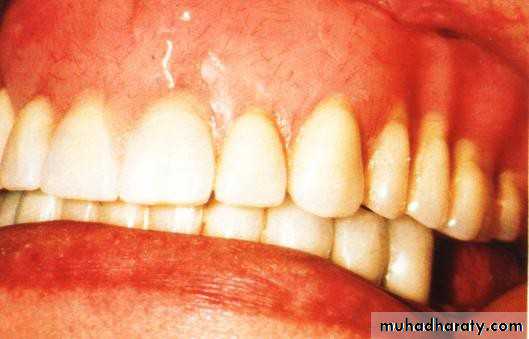

• abutment preparation”• 1- Simple tooth reduction of vital abutment. 2- Tooth reduction and cast coping of

• vital

• abutment / thimble or dome- shaped.

• 1- Simple tooth modification of vital abutment.

• A- Thimble-shaped

• coping• 2- Tooth reduction and cast coping of vital abutment